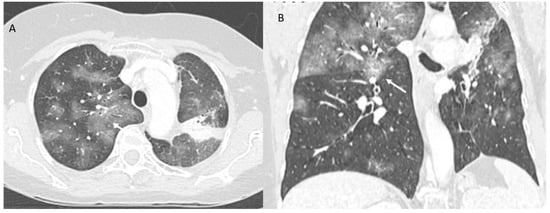

2.1. COVID-19 Vaccine Radiation Recall

| Type of Pneumonia | Lung Involvement | CT-Patter |

|---|---|---|

| COVID-19 Pneumonia | Diffuse (related to the phase of disease) | ground-glass opacity, crazy-paving pattern, consolidative opacities, interlobular septal thickening (according to the phase of disease) |

| RRR-Related Vaccine | Target Area | Consolidative opacities |

| Pulmonary lymphangitis carcinomatosa | Diffuse (related to the phase of disease) | Irregularly interlobular septal thickening, smooth (early stage), or nodular thickening (late development), ground-glass opacity, pleural effusions. |

| ICI-Related Pneumonitis | Diffuse (related to the phase of disease) | ground-glass and reticular opacities, consolidative opacities, interlobular septal thickening, “crazy-paving” pattern |